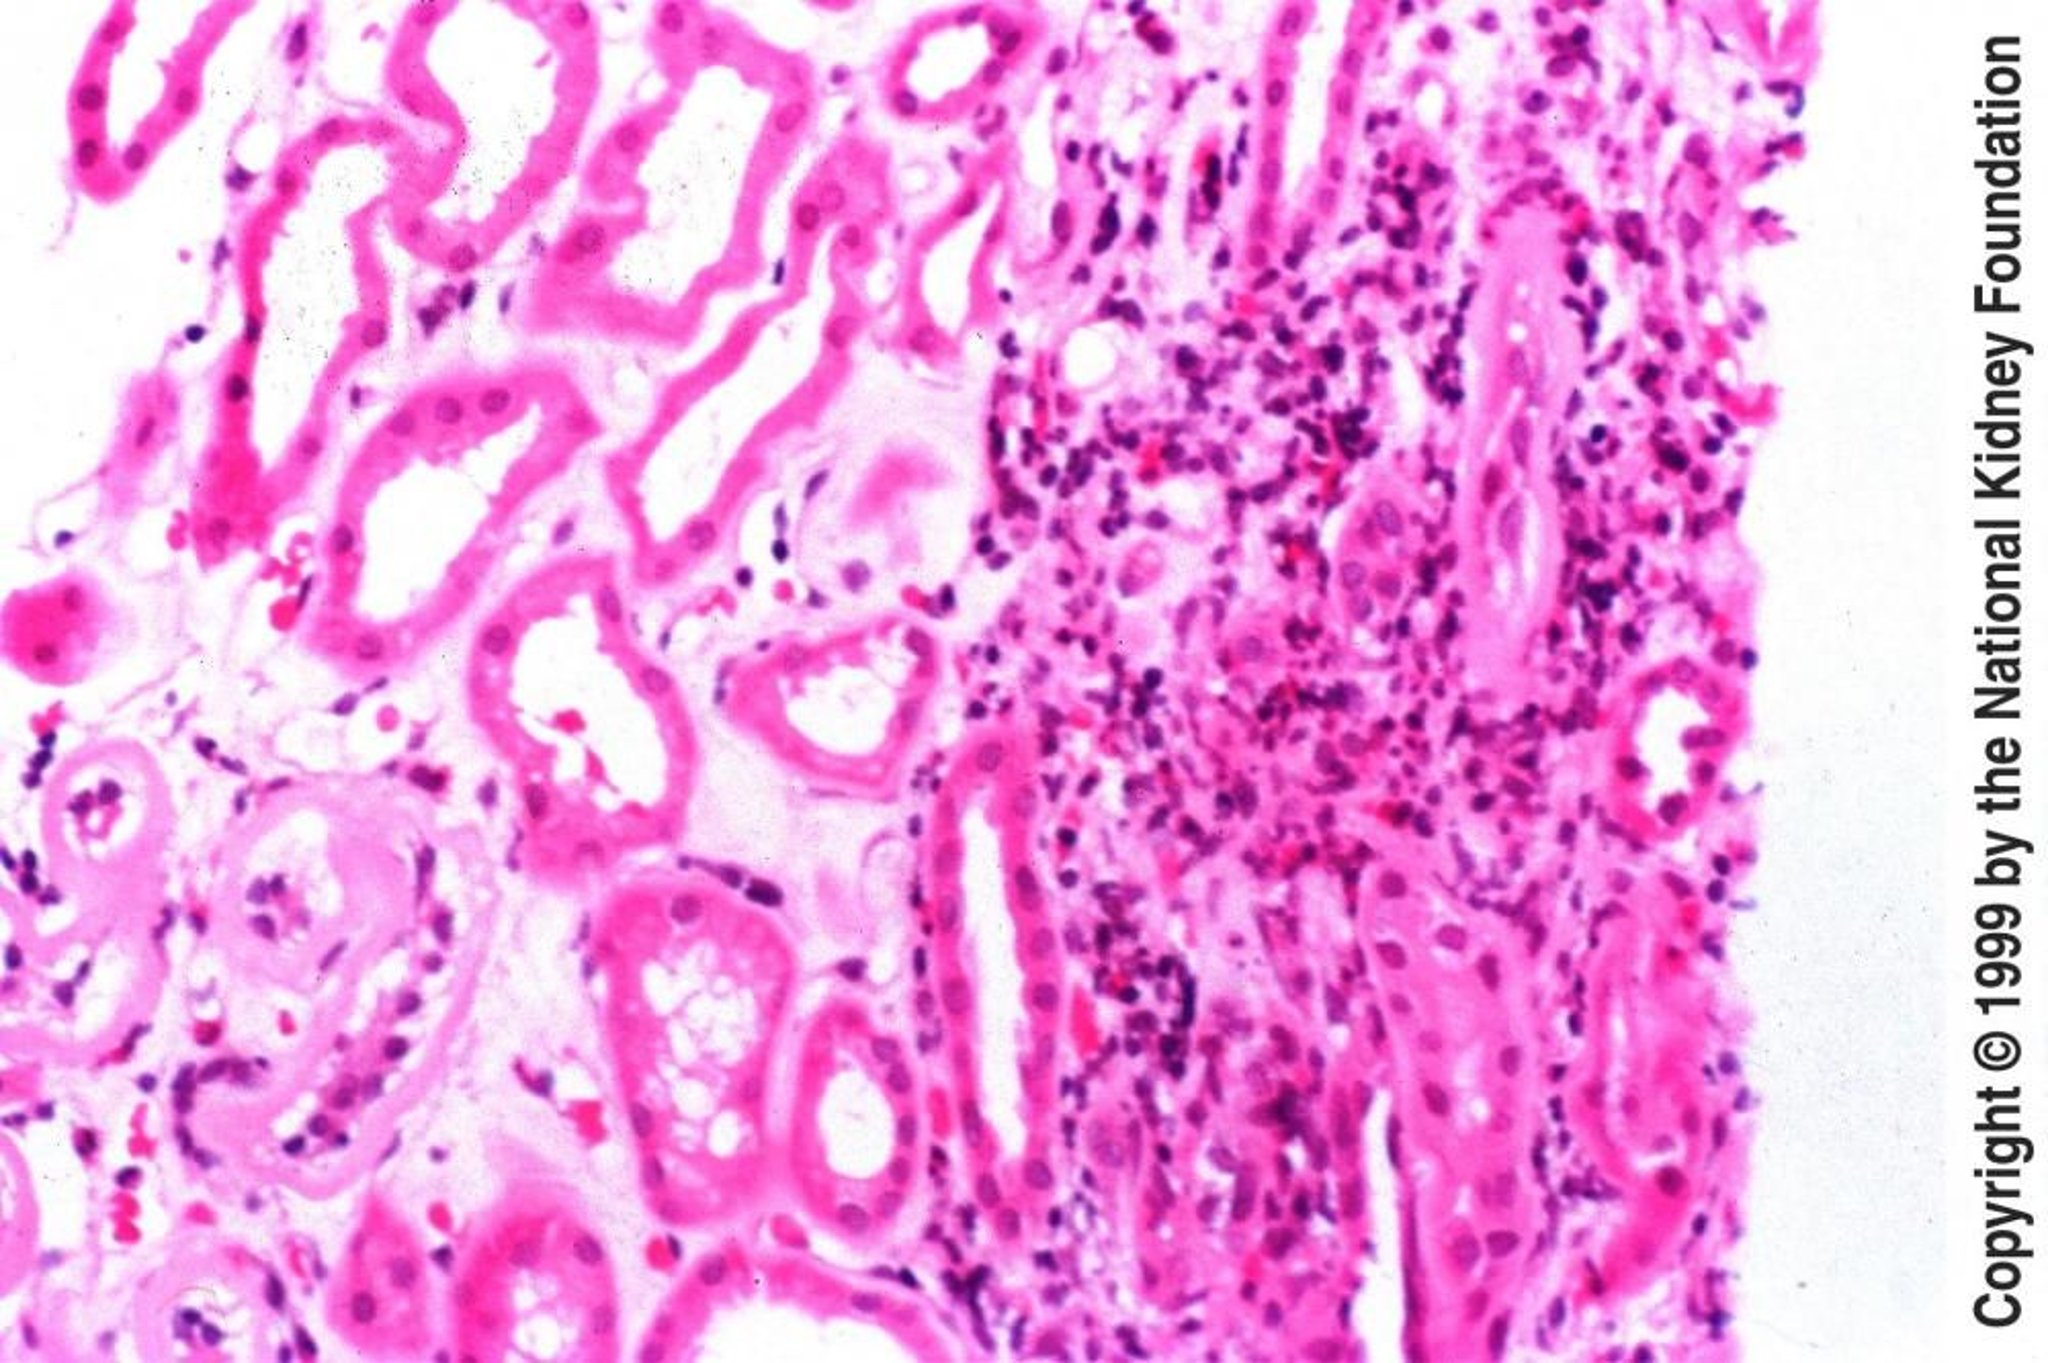

Bei akuter tubulointerstitieller Nephritis sind Glomeruli meist normal. Der früheste Befund ist ein interstitielles Ödem, typischerweise gefolgt von einer interstitiellen Leukozyteninfiltration (mit Lymphozyten, Plasmazellen, Eosinophilen und einigen polymorphkernigen Leukozyten). In schweren Fällen kann man Entzündungszellen erkennen, die in den Raum zwischen den Zellen der tubulären Basalmembran eindringen (Tubulitis). Bei anderen Proben kann eine granulomatöse Reaktion aufgrund der Exposition gegenüber Beta-Lactam-Antibiotika, Sulfonamiden, Mykobakterien und Pilzen erkennbar sein. Das Vorhandensein nichtverkäsender Granulome spricht für eine Sarkoidose. Eine lymphoplasmozytäre Infiltration des Niereninterstitiums mit korbgeflechtartiger (storiformer) Fibrose lässt auf eine IgG4-bedingte tubulointerstitielle Nephritis schließen. Die Immunfluoreszenz- oder Elektronenmikroskopie deckt nur selten irgendwelche pathognomonischen Veränderungen auf.

Bei chronischer tubulointerstitieller Nephritis wird eine Nierenbiopsie zu diagnostischen Zwecken nicht oft durchgeführt. Wenn jedoch Bedenken hinsichtlich alternativer Diagnosen bestehen, könnten diese weiterverfolgt werden. Glomeruli variieren von normal bis vollständig zerstört. Die Tubuli können fehlen oder atrophiert sein. Die tubulären Lumina variieren im Durchmesser, können aber eine starke Dilatation mit homogenen Zylindern aufweisen. Das Interstitium enthält in unterschiedlichem Maße entzündliche Zellen und Fibrosen. Nichtnarbige Regionen erscheinen fast normal. Im Ganzen sind die Nieren klein und atrophisch.